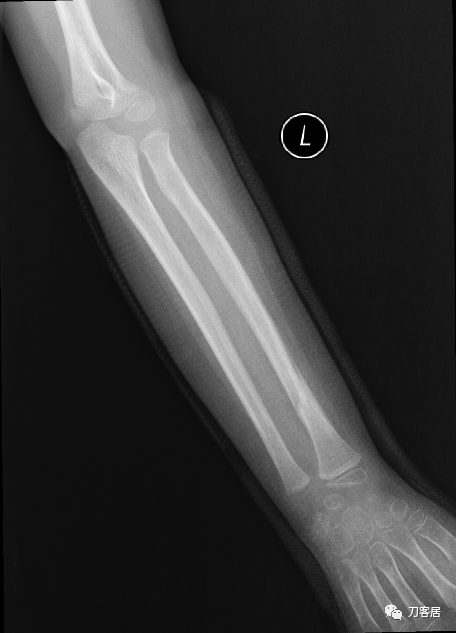

2021年7月22日晚,上海美华医院儿童骨科的师东良医生,给我提供了一例他处理的严重移位尺桡骨双骨折病例,经过手法复位,石膏外固定治愈。这个病例,其他医院建议要做手术。实际上,这样的病例,在现实中有太多太多,因为手法复位,石膏外固定治疗骨折,这是骨科医生的基本功。

下面为师东良医生提供的病例:

超声引导下闭合手法复位石膏外固定治疗7岁患儿尺桡骨远端移位双骨折。

男,7岁,左前臂远端桡尺骨双骨折,术前X光片见图1,行超声引导下闭合复位石膏外固定术,康复训练,6周拆石膏,随访2.5月的效果。术后2.5X光片见图23。功能上仅前臂旋后较健侧减小15°,继续加强康复训练中。家长满意,评价见图4

1. 超声引导下闭合复位石膏外固定术左尺桡骨双骨折

2. 超声引导下闭合复位石膏外固定术后2.5月左前臂正位X光片

3. 超声引导下闭合复位石膏外固定术后2.5月左前臂侧位X光片